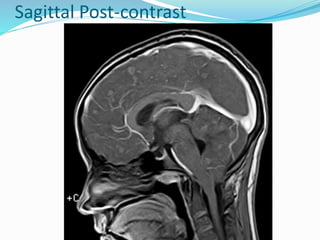

65 yrs. Old male

complaints of unexplained progressive neurological symptoms

Dx – NCC.

Post-contrast

Vesicular & colloid vesicular stage